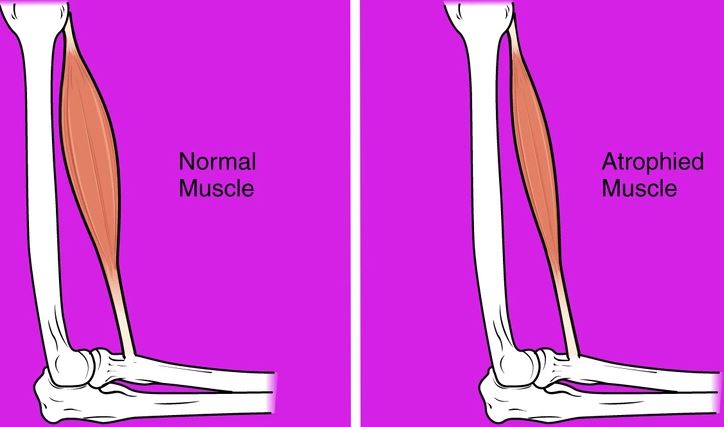

#8 Svalová atrofia

V mikrogravitácii už svaly neunesú takú váhu ako na Zemi, čo vedie k atrofii svalov. Astronauti môžu stratiť až 20 % svalovej hmoty už za 5 až 11 dní bez pravidelného cvičenia. Členovia posádky proti tomu denne približne dve hodiny cvičia pomocou špecializovaných zariadení, ako sú bežecké pásy a odporové zariadenia. Napriek tomuto úsiliu je určitý úbytok svalovej hmoty nevyhnutný, čo si vyžaduje rehabilitáciu po návrate na Zem.